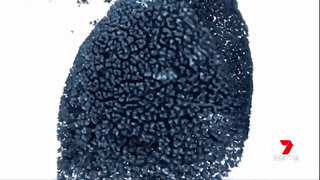

澳洲的科學(xué)家們通過運用納米技術(shù),將“基因沉默”(gene silencing)藥物運送至腫瘤細(xì)胞中來治療胰腺癌。

藥物已經(jīng)在擁有和人類相仿的瘢痕組織的小鼠身上進行試驗,并獲得成功。